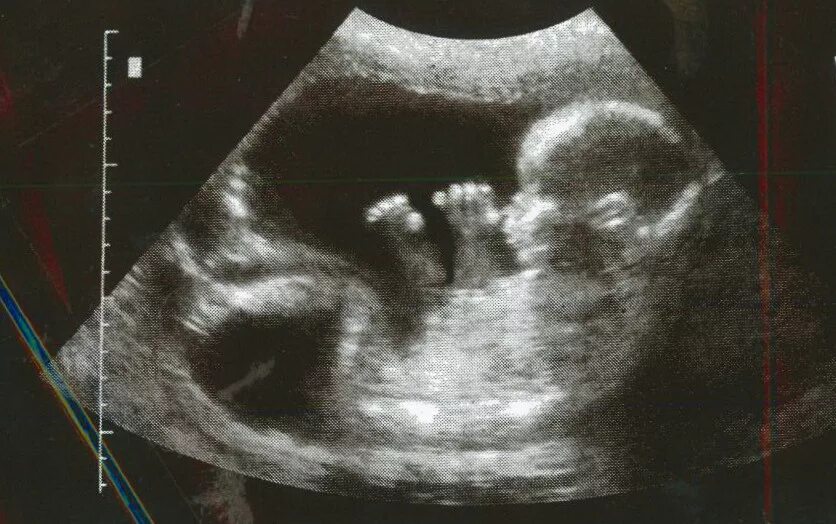

Ребенок в 20 недель беременности в животе